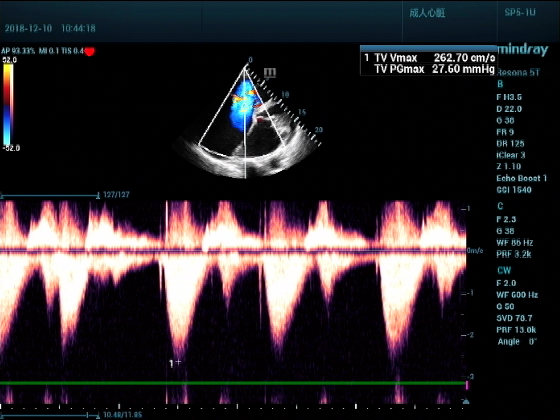

男,81岁,全身浮肿来住院

超声可见:左房,右房,右室明显增大,主肺动脉及右肺动脉增宽,二尖瓣中度反流,三尖瓣重度反流,肺动脉轻度高压,心律不齐

心包积液盆腔积液。淤血性肝增大,肝静脉增宽。(右心衰声像改变)